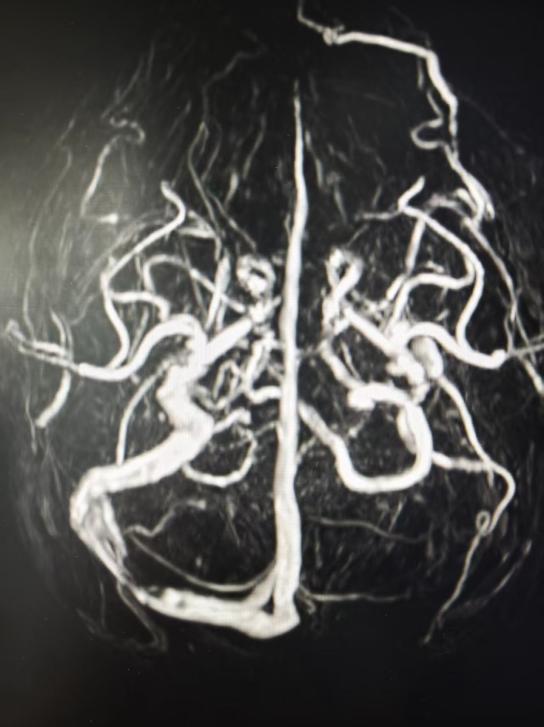

患者系26岁男性,发作性头痛1周余。术前感染、免疫、生化及脑脊液常规检查无明显异常。行头部MRV检查,显示左侧横-乙状窦发育纤细、右侧横窦局限性狭窄,考虑为特发性颅高压伴静脉窦狭窄。